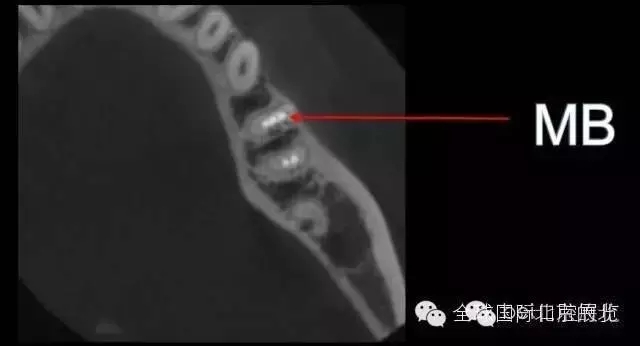

DB,DL.根管充填完成,樹(shù)脂封閉根管口,繼續(xù)探索未知的近中隱藏根管,所以決定拍1/4 CBCT確認(rèn)MB存在,

證實(shí)確實(shí)是遺漏了MB,

是遺漏了,但是又有新的問(wèn)題出現(xiàn),無(wú)法找到根管口,我一般會(huì)用8#Kfile去尋找根管,CBCT上看就在眼前,但是我就是看不到,也無(wú)法進(jìn)入,此時(shí)操作也快一個(gè)小時(shí)了,患者也覺(jué)得累了,所以MB暫且停止尋找,因?yàn)橐泊_實(shí)無(wú)法進(jìn)入,所以把ML,MM根充完成,準(zhǔn)確測(cè)量長(zhǎng)度,AH-Plus,根管糊劑,涂布根管壁,冷牙膠依次充填完成暫封,下周繼續(xù)尋找失落的根管,同時(shí)也要把頰側(cè)楔缺的位置封閉好,防止再感染,再?zèng)]有橡皮障的保護(hù)下盡量減少感染機(jī)率。

去除暫封物繼續(xù)尋找MB,繼續(xù)尋找之前,用樹(shù)脂將根充完成的DB,DL根管口封閉,MB的位置暫時(shí)先不封,防止堵塞MB,剛開(kāi)始還是找不到MB,然后從頰側(cè)的楔狀缺損入手才得以發(fā)現(xiàn)MB的入口,把楔缺擴(kuò)大去腐干凈。

終于找到MB了,然后把根管口MM,ML封閉,S3機(jī)擴(kuò),F(xiàn)1.04錐度牙膠試尖,期盼了好久的柳暗花明終于出現(xiàn)。